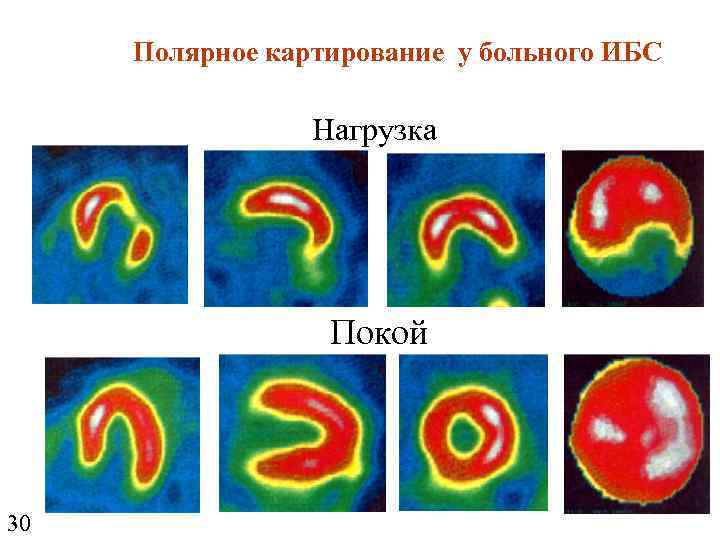

Полярное картирование у больного ИБС Нагрузка Покой 30

Полярное картирование у больного ИБС Нагрузка Покой 30

Полярное картирование у больного ИБС

Полярное картирование у больного ИБС